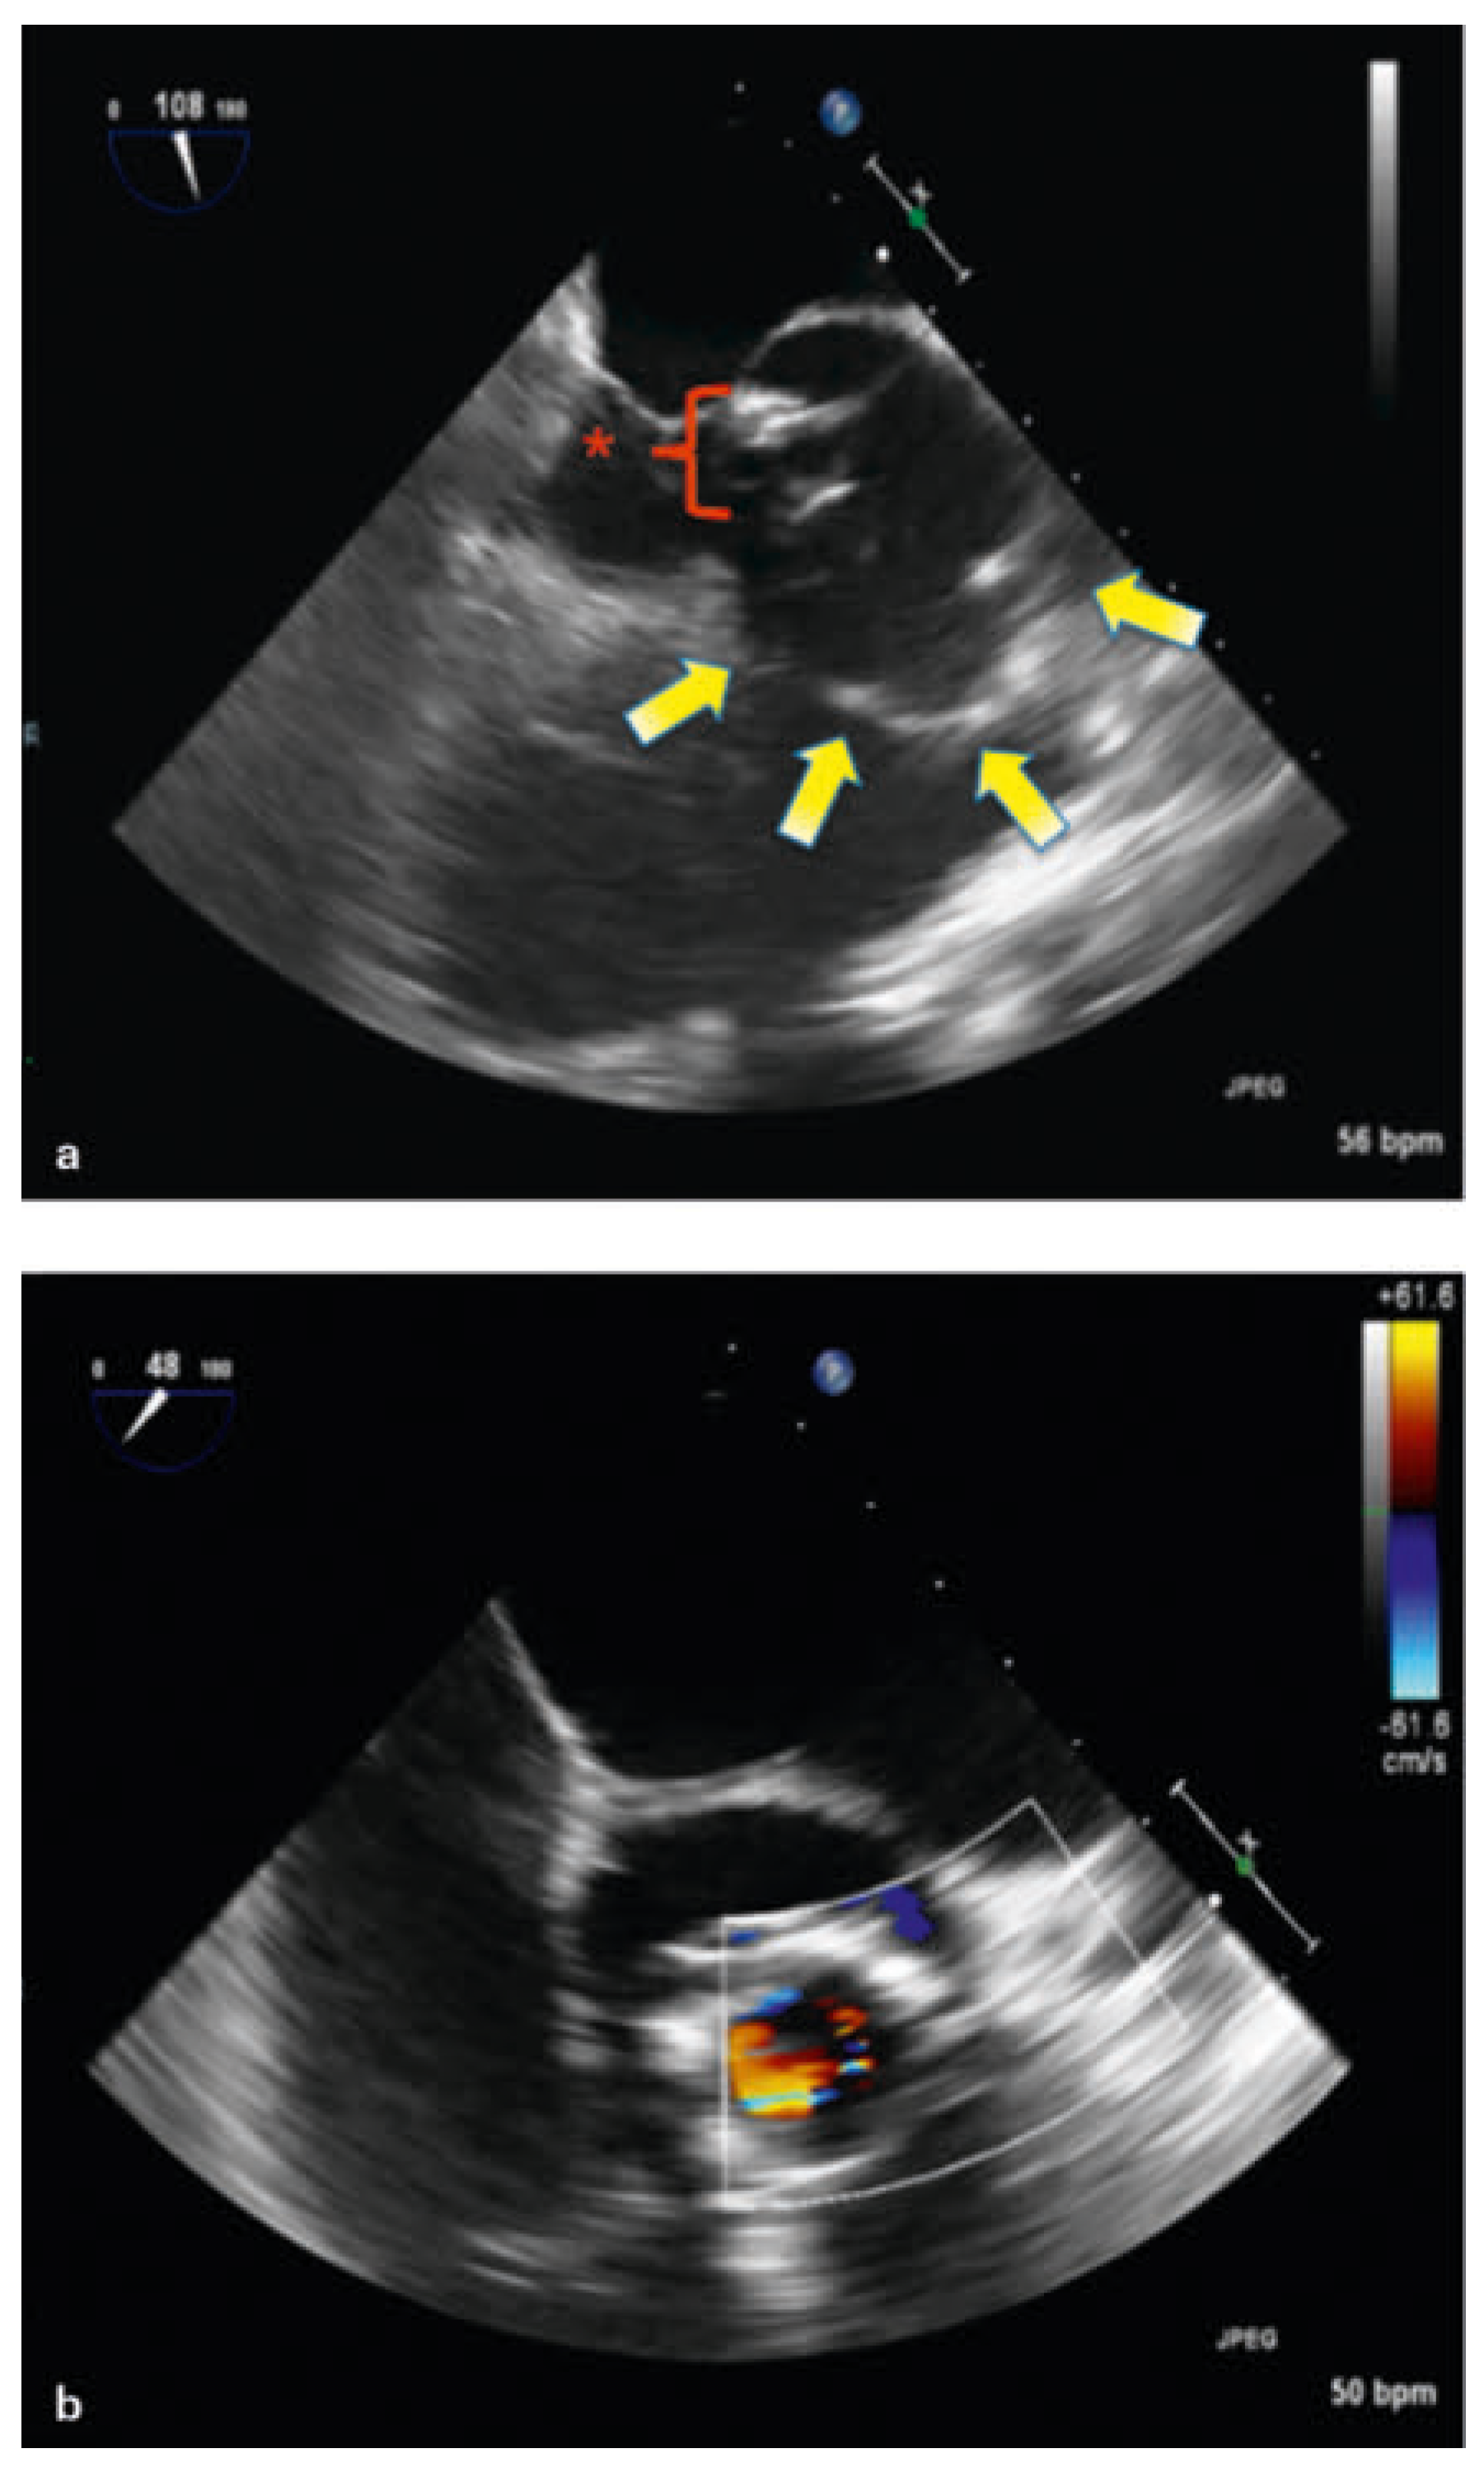

Intraoperative echocardiography showed a disconnection of the aortic valve prosthesis with a huge abscess surrounding the annular area (Figure 3a,b). For the first time, aortic insufficiency was diagnosed (Figure 3b). The biological aortic prosthesis could be removed without any difficulty only by elevation with forceps from the right coronary sinus, where the insufficiency was detected before. A large annular abscess had to be eradicated (Figure 4). Afterwards, a biological freestyle aortic root prosthesis (Freestyle, Medtronic) was implanted to avoid as much artificial material as possible. Additionally, epicardial pacemaker wires for the right atrium and right ventricle were implanted during the operation because of the high risk of atrioventricular block after eradication of the huge abscess.

Figure 3. a: TOE on operation day: moving aortic prosthesis indicating suspected annular disconnection (red arrow) inside a huge abscess (yellow arrow). b: TOE on operation day: severe, periannular insufficiency.